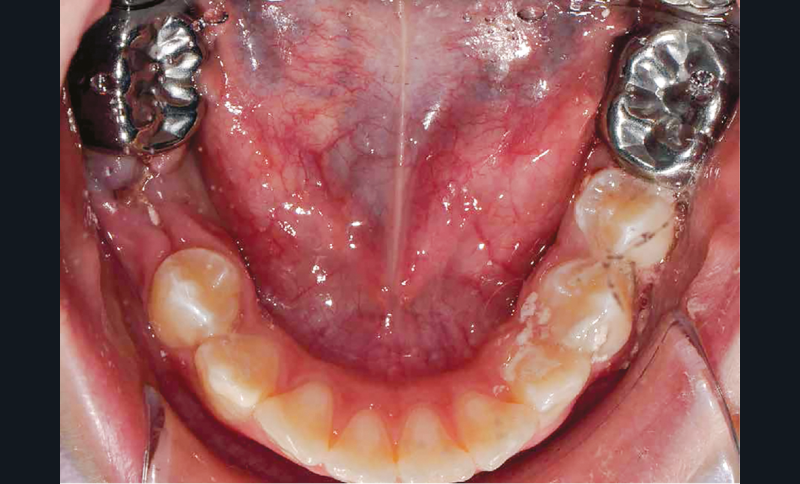

Il a été décidé de réaliser des coiffes préformées métalliques sur les premières molaires permanentes pour supprimer les sensibilités et restaurer les fonctions mécaniques. Au regard de l’immaturité des tissus parodontaux et de l’anxiété de Lisa, la réalisation d’onlays n’a pas été envisagée.

Afin d’optimiser les séances de soins, l’anesthésie intra-osseuse par injection électronique a été réalisée avec le Quicksleeper 5® dans les deux secteurs (fig. 3 et 4) afin de permettre la réalisation des coiffes préformées métalliques sur 36 et 46 dans la même séance (fig. 5 à 7). Il aurait été difficilement envisageable de réaliser les coiffes dans la même séance en utilisant une anesthésie tronculaire dans chaque secteur.